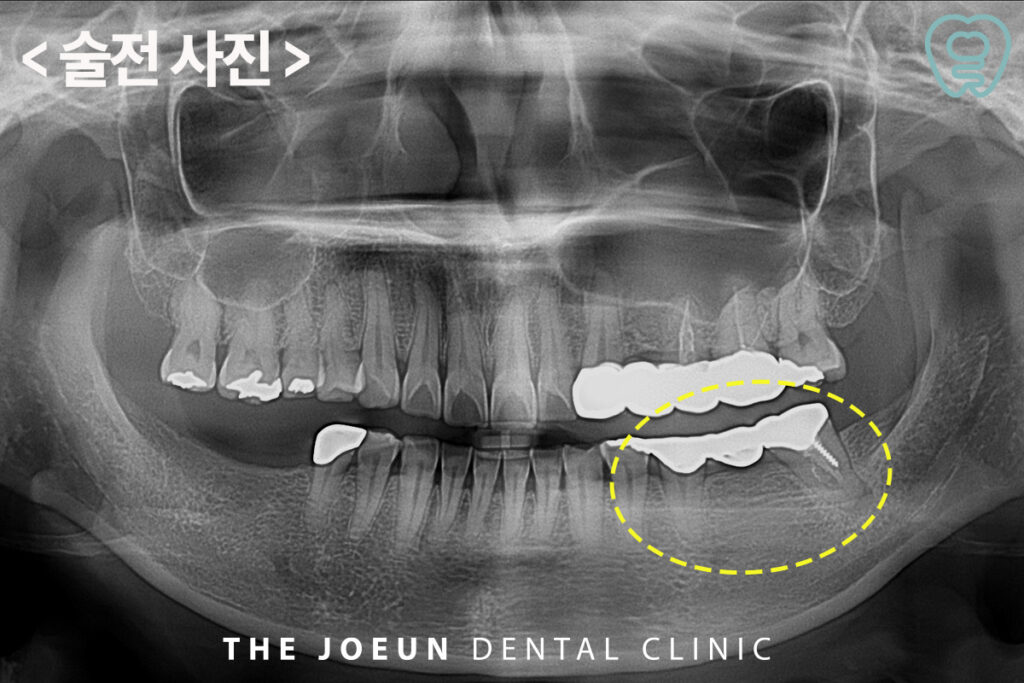

환.자분께서는 며칠 전부터 왼쪽 아래 치아에 불편감이 느껴지신다며 내원해 주셨는데요. 파노라마 촬영 결과 왼쪽 아래 작은 어금니와 가장 안쪽의 큰 어금니까지 연결되어 있는 브릿지 보철물의 상태가 좋지 않아 큰 어금니는 발치 후 기존의 첫 번째 큰 어금니가 없는 자리까지 두 개의 임플란트 식립을, 앞쪽의 작은 어금니는 발치를 진행할 정도는 아니라고 판단되어 신경치료 후 크라운 수복 계획을 수립하였습니다.